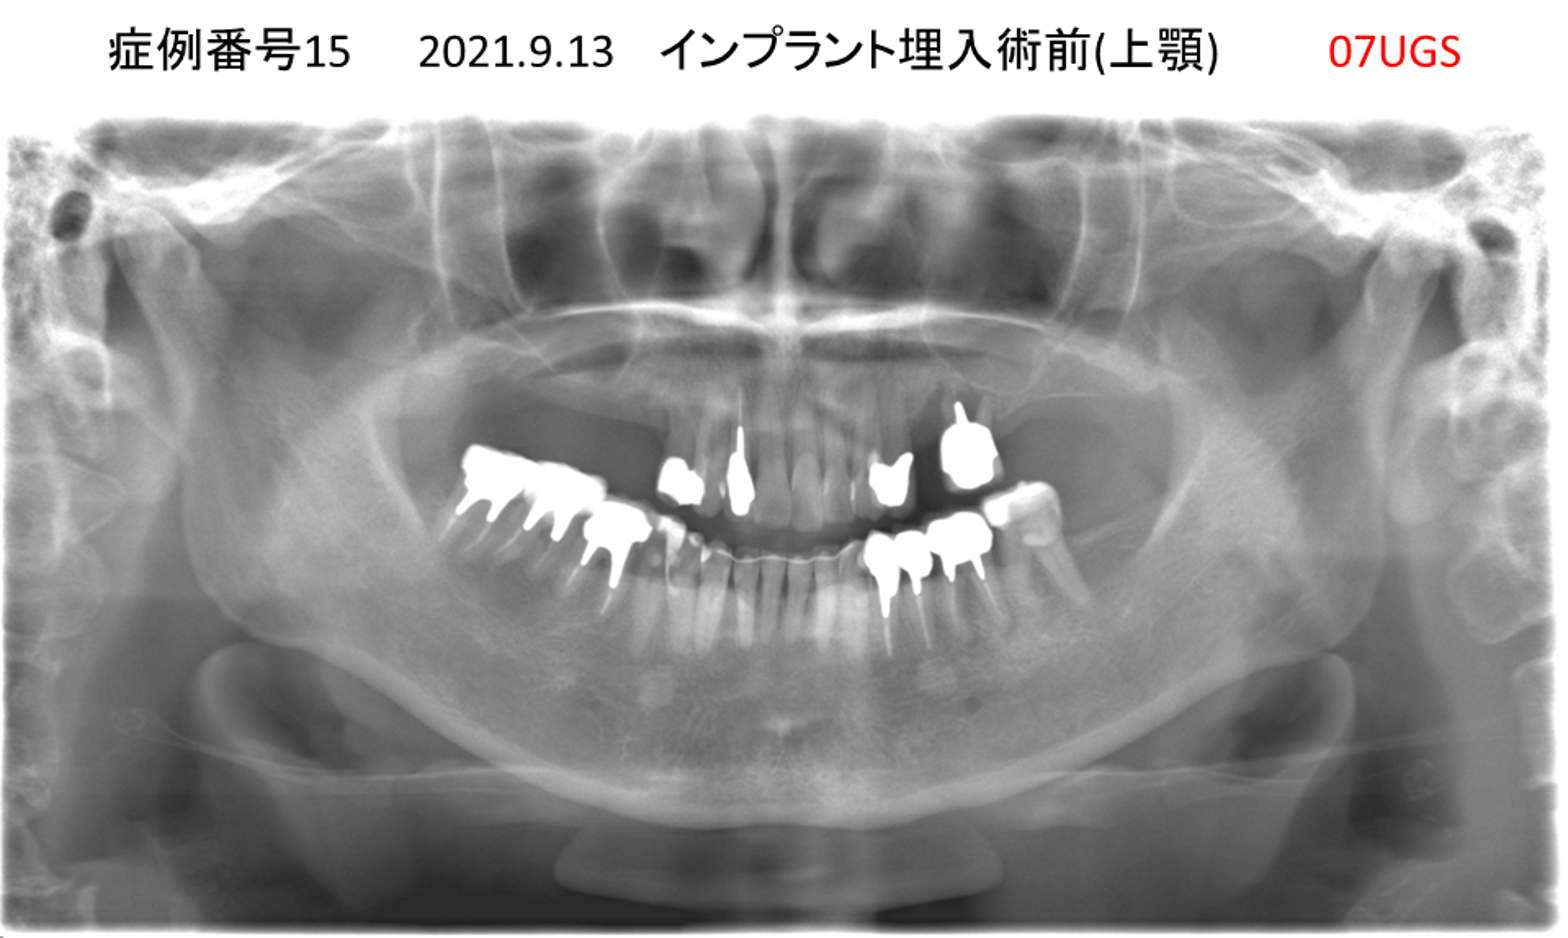

上の前歯が揺れていて痛い患者様のインプラント症例

| 治療名称 |

インプラント |

| 治療費用 |

295万円+税 |

| 治療期間 |

6か月 |

| 患者さんの症状(主訴) |

上の前歯が揺れていて痛い |

| 治療内容 |

抜歯即時インプラント |

| 治療結果 |

痛みがなく、しっかり噛める。 見栄えがとても良い |

| 治療の注意点(リスク/副作用) |

インプラントが壊れたら再治療が必要 |